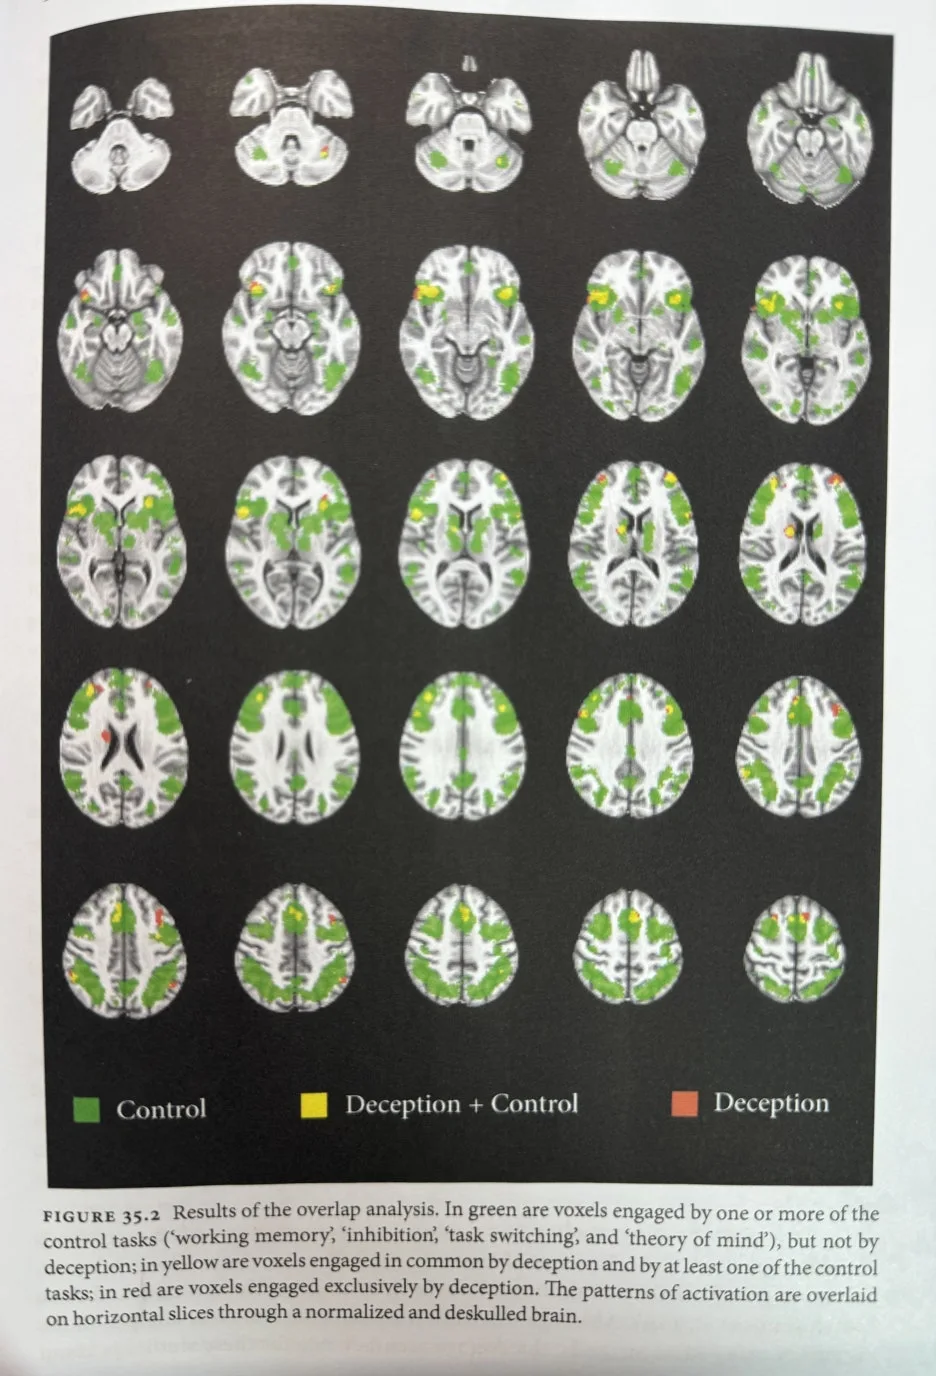

위 거짓말의 3단계는 각각 다른 부위의 뇌 활성화와 연관되어 있습니다. 이 영역은 연구마다 차이가 있지만 주로 전두정엽(fronto parietal cortex), 내측전전두엽(medial prefrontal cortex), 복내측전전두엽(ventromedial prefrontal cortex), 배외측 전전두엽(dorsolateral prefrontal cortex), 전측대상회 피질(anteror cingulate), 뇌섬엽(insual cortex), 아래마루소엽(inferior parietal lobule), 모서리위이랑(supramarginal gyrus) 등이 거짓말과 연관된 것으로 알려져 있습니다. 많은 영역이 포함되는 만큼 이 영역들은 거짓말에만 특별히 활성화되는 것이 아닙니다. 이 영역들은 주로 사람이 논리적으로 말을 전개할 때 활성화되는 영역들이기도 합니다. 즉 거짓말과 논리적인 말은 한 끗 차이라는 의미가 될 수 있습니다.

IMG_1419_-_%EB%B3%B5%EC%82%AC%EB%B3%B8.jpg?type=w1 거짓말할 때 활성화되는 뇌의 영역들.

하지만 아래마루소엽(inferior parietal lobule), 모서리위이랑(supramarginal gyrus)은 거짓말에 특별히 활성화되는 영역입니다. 아래마루소엽은 주로 자기 참조의 영역, 도덕적 사고의 영역이고 모서리위이랑은 감정적인 반응과 언어 표현의 영역입니다. 앞으로 더 많은 연구가 필요하겠지만 개인적으로 해석해 보자면 이 영역이 활성화된다는 것은 거짓말을 할 때 양심의 가책을 느끼며 감정의 소용돌이에 빠진다는 결과로도 볼 수도 있을 것 같습니다. 또한 거짓말을 할 때는 '자기'가 어떤 사람인지 되뇌는 것으로도 볼 수 있지 않나 생각해 봅니다.